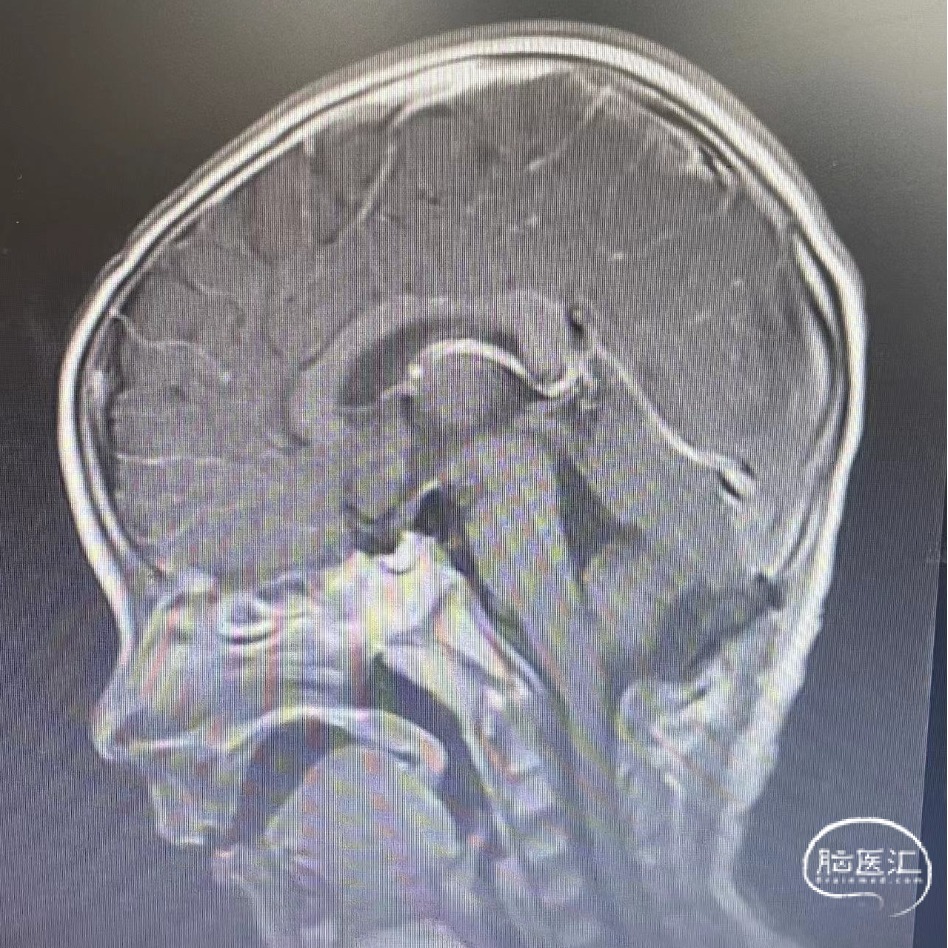

术前头部磁共振扫描

头部MRI平扫增强显示:脑干背侧-四脑室内可见一团块状短-长T1短-长T2信号肿块,较大层面大小约为2.9cm*2.6cm*2.4cm,第四脑室内病灶增强后未见强化,右侧小脑半球可见增粗、弯曲血管影,周围脑实质可见轻度片状水肿。慕上脑室轻度扩张积水。考虑海绵状血管瘤并出血可能。